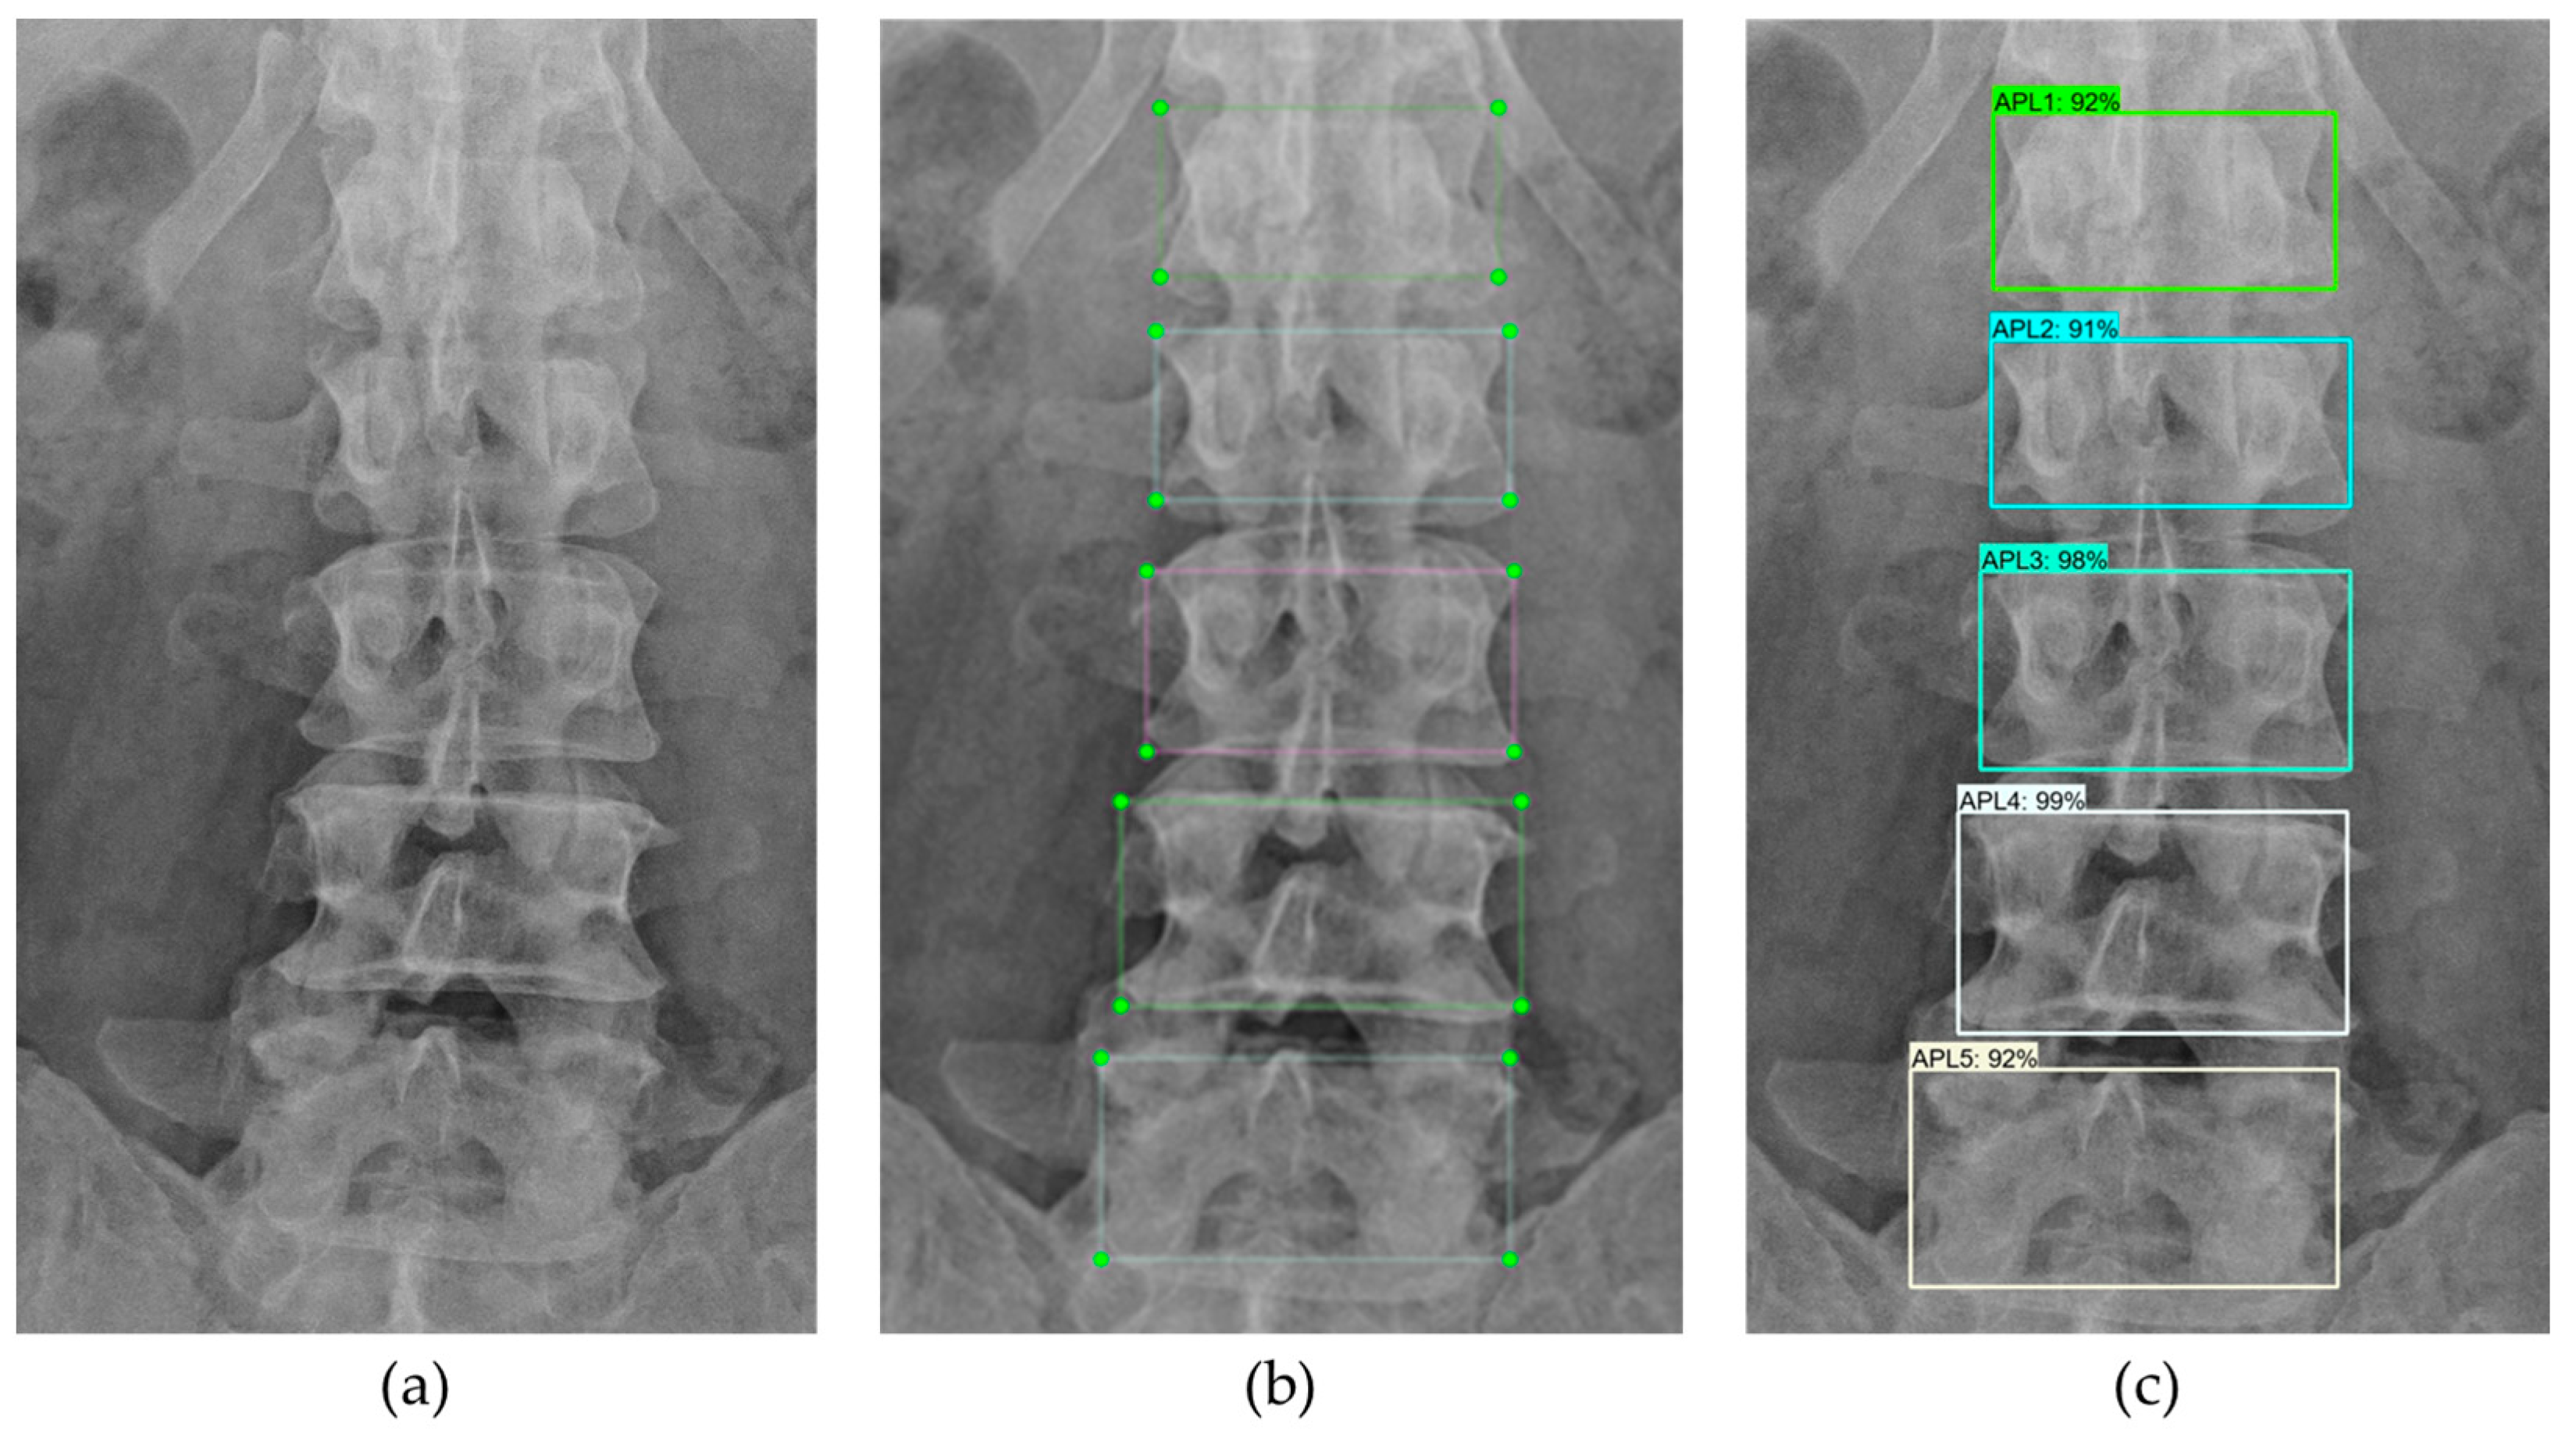

2.4.1. Lumbar Vertebrae Detection

The targets of lumbar vertebrae detection experiment were detecting bounding boxes around vertebral bodies. The processes of this experiment are shown in Figure 6. The input was raw X-ray images, as shown in Figure 7a. We separated BUU-LSPINE into training and testing sets with a 0.8:0.2 ratio. The bounding boxes’ ground truth of the detection was created using corner points’ ground truth, as shown in Figure 7b. Then, we trained YOLOv5, MobileNetV1, MobileNetV2, ResNet50V1, ResNet101V1, ResNet152V1, ResNet50V2, ResNet101V2, ResNet152V2, EfficientDet D0, and EfficientDet D1 models, with a batch size of 4, a learning rate of 0.04, and all images resized to 640 × 640 pixels. The targets were bounding boxes of five vertebrae (‘APL1’, ‘APL2’, ‘APL3’, ‘APL4’, and ‘APL5’) on AP view and (‘LAL1’, ‘LAL2’, ‘LAL3’, ‘LAL4’, and ‘LAL5’) on LA view. Since the human spine typically consists of five lumbar vertebrae, our model chose only one candidate with the highest likelihood from each class. We stopped our training process early when there was no further improvement in precision. The detection results are shown in Figure 7c.

Figure 7.

Detection of lumbar vertebrae: (a) input image; (b) ground truth; (c) detection.